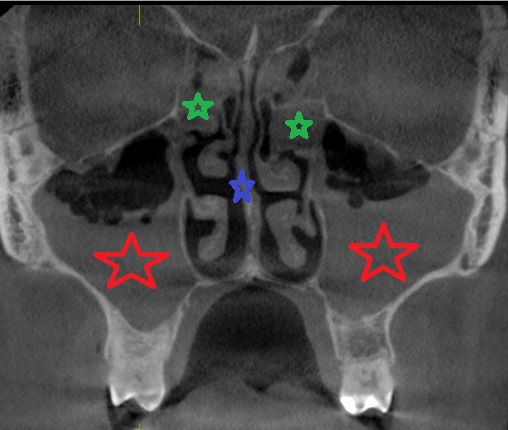

КТ-снимки хронического этмоидита: подробная визуализация